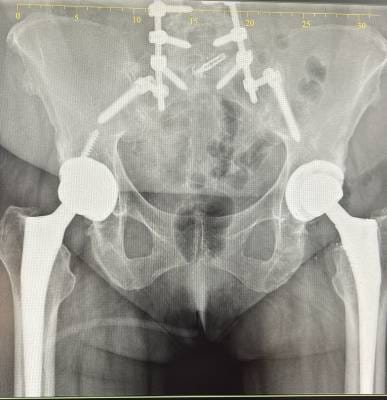

I had a Total hip replacement surgery with Dr. Haytham , and I am extremely happy with the result. I was able to walk on the same day of the operation, which was truly amazing. Now, one month after the surgery, I feel a great improvement. I have come back to life — I can walk every day after being unable to walk before, and I’ve regained all my muscle strength. Dr. Haytham’s team was incredibly professional and supportive; they didn’t leave me alone for a moment. I’m very thankful to Dr. Haitham and his wonderful team for their excellent care.